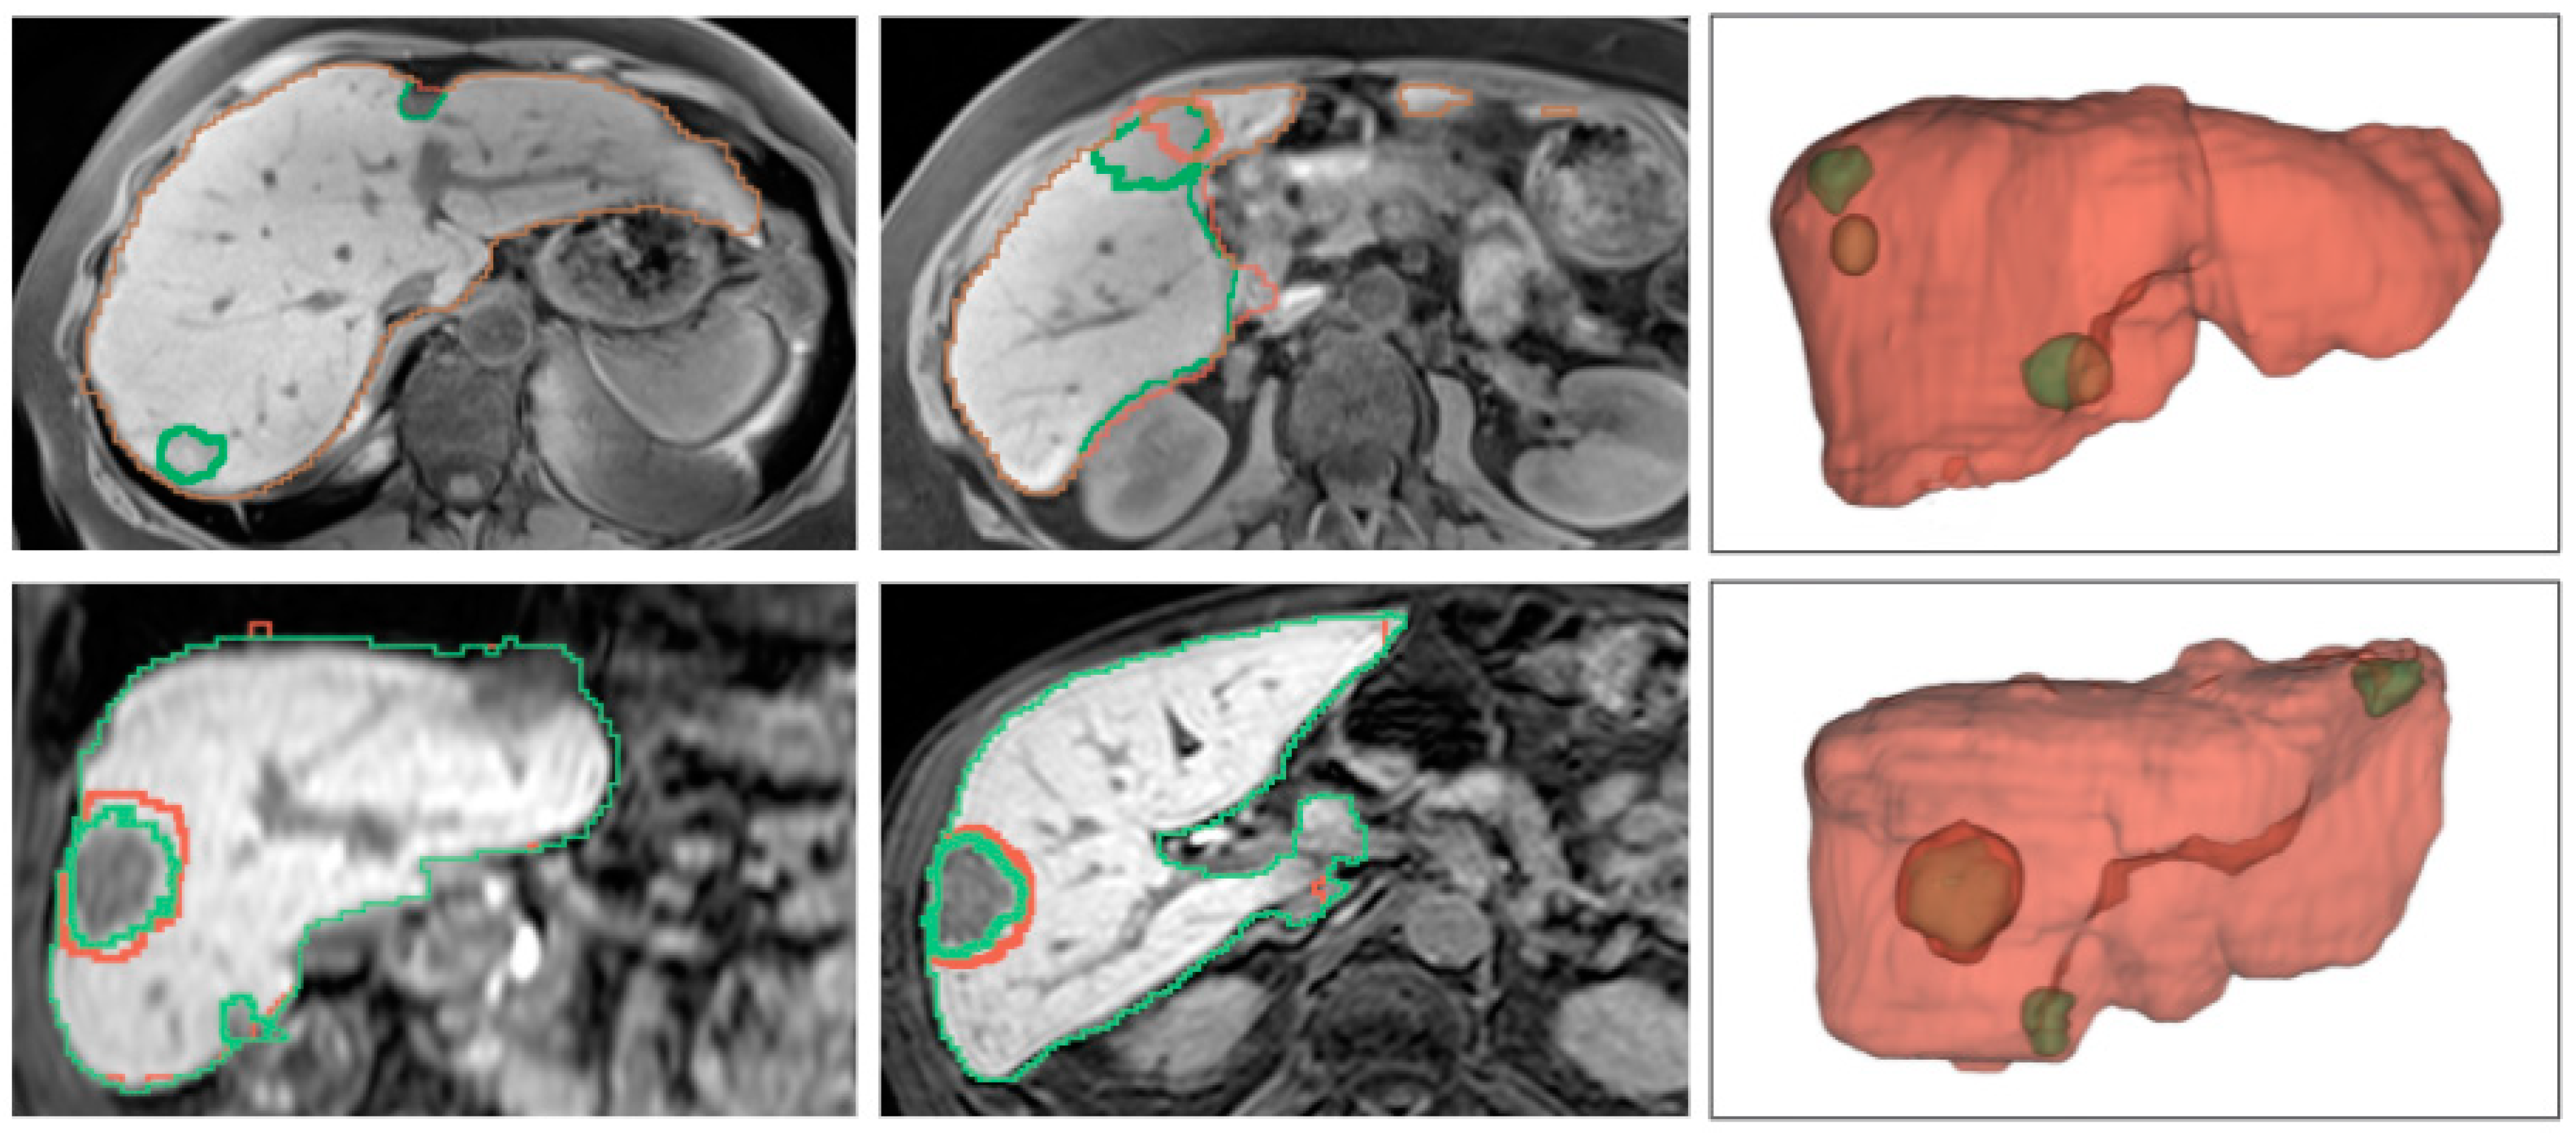

4.2.2. Qualitative Results